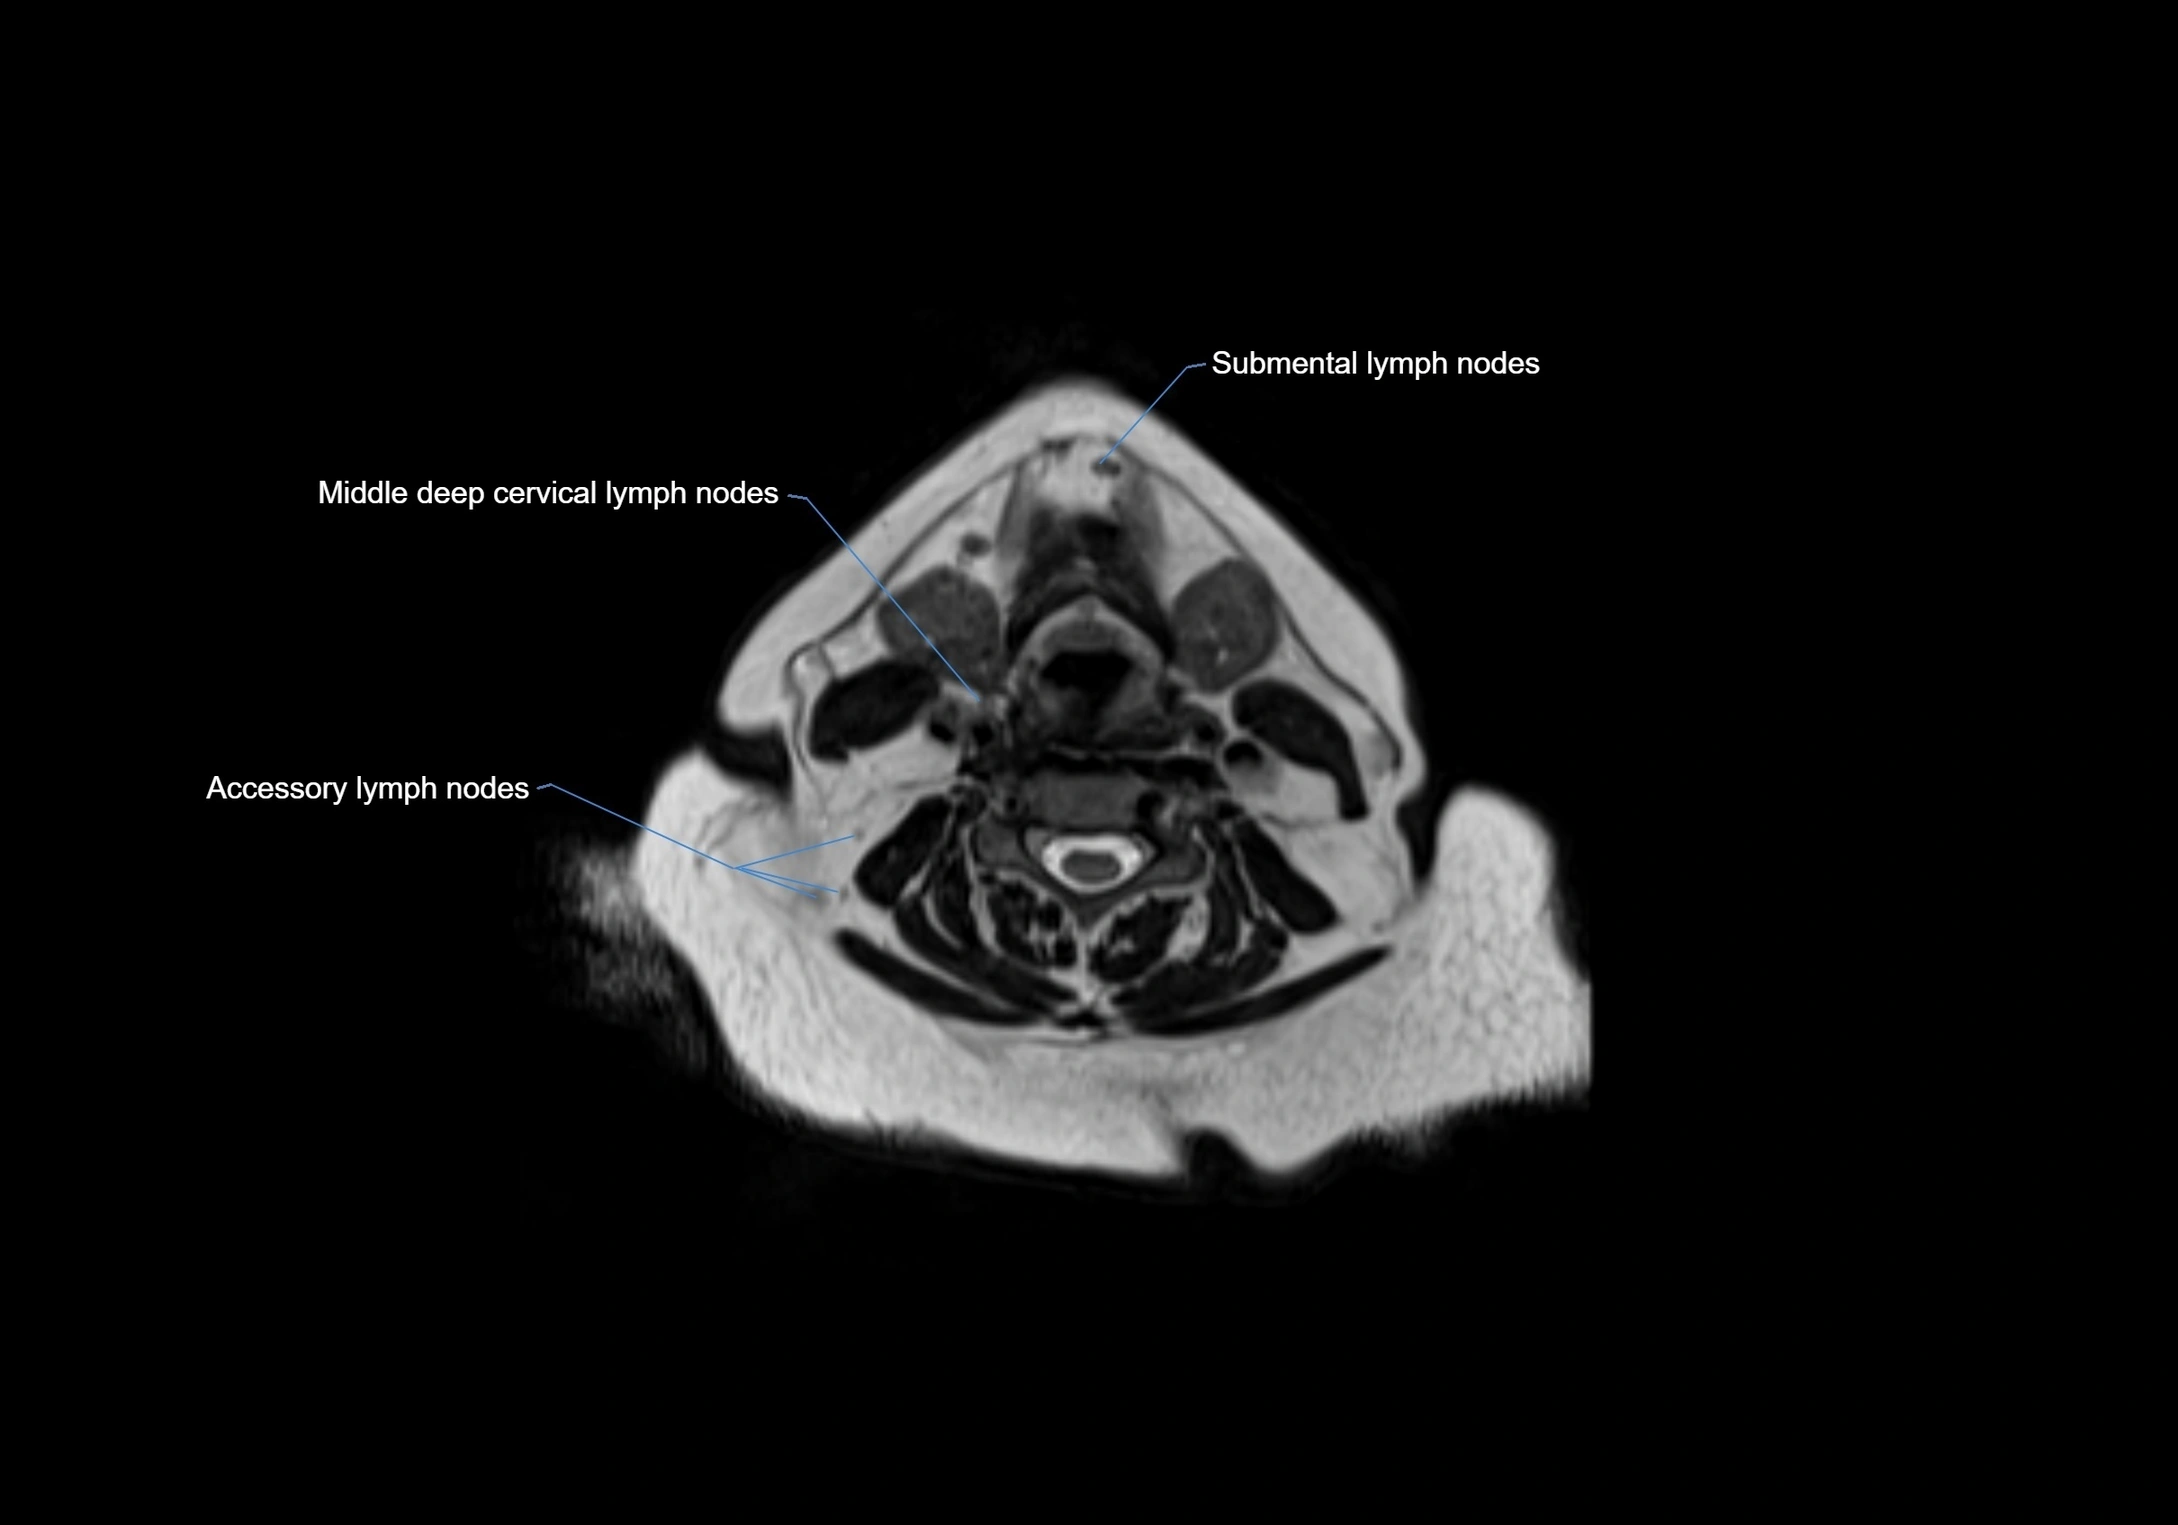

Accessory lymph nodes are small, secondary lymph nodes located along the main facial and cervical lymphatic chains, often adjacent to primary lymph nodes, such as preauricular, submandibular, or occipital nodes. They are typically less than 5 mm in diameter, embedded within subcutaneous fat or connective tissue, and may be variable in number and location. These nodes provide additional filtration and immune surveillance for lymph collected from the face, scalp, and neck regions. Accessory lymph nodes are usually non-palpable in healthy individuals but may enlarge in response to infection, inflammation, or metastasis, making them clinically significant.

Location

• Found along primary lymph node chains, including preauricular, submandibular, parotid, and occipital regions

• Embedded in subcutaneous fat or superficial fascia, often lateral or posterior to primary nodes

• Variable in number; may occur unilaterally or bilaterally, depending on individual anatomy

MRI images